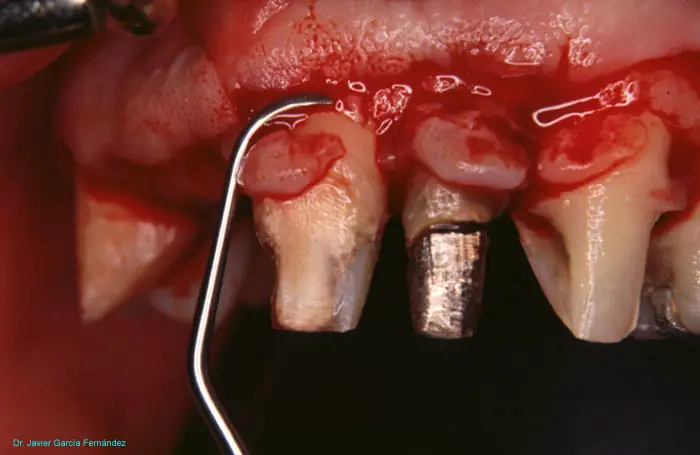

Atlas of Surgical Techniques in Periodontics. Chapter III. Atlas de Técnicas Quirúrgicas en Periodoncia